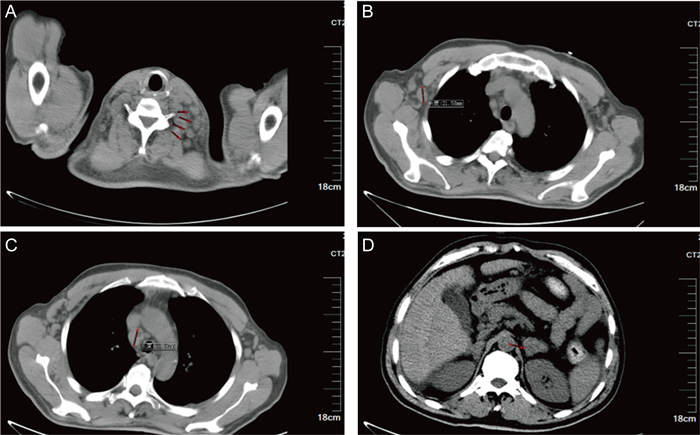

1.2 检查结果进一步完善检查,结果如下。β-D-葡聚糖(β-D-glucan, G)试验:127 pg/mL,半乳甘露聚糖(galactomannan, GM)抗原试验:1.67 s/co;头颅、鼻咽部及颈部磁共振成像(magnetic resonance imaging,MRI)提示:延髓左侧异常信号,不排除转移性病变,前颈部多发淋巴结,部分肿大、融合(见图 2)。喉镜提示:双侧圆枕见新生物,其表面覆盖白色伪膜样物,左侧咽侧壁、舌根部隆起,左侧声带后上方见囊肿样物,双侧梨状窝光滑,左侧声带固定,右侧声带运动正常(见图 3)。2次颈部及腋窝淋巴结穿刺涂片见细胞内外大量圆形、卵圆形直径约2~4 μm的孢子,多呈两头钝圆、中间有横膈的腊肠形,考虑为马尔尼菲篮状菌病(见图 4)。与此同时血培养瓶内涂片镜检下见丝状真菌生长。随后,将淋巴结穿刺物分别在25 ℃和37 ℃沙保罗培养基中培养1周,观察到在25 ℃培养条件下,菌落呈黄绿色,并见红色可溶性色素深入培养基中,显微镜下见典型的扫帚状有隔菌丝及端生分生孢子;在37 ℃培养时,菌落为白色、褐色奶油状,无色素产生,显微镜下呈带横隔的腊肠形孢子(见图 5)。

| Laryngoscopy showed neoplasm in bilateral round occipital, the surface of which was covered with white pseudomembranous material, and the left lateral pharyngeal wall and tongue base were raised, cyst-like material was seen behind and above the left vocal cord. The bilateral piriform fossa was smooth, the left vocal cord was fixed, and the right vocal cord movement was normal. 图 3 患者喉镜下表现 Fig. 3 Laryngoscopic findings |

本例报道中,患者起初仅表现为“咽痛”,经鼻咽镜及喉镜检查发现鼻咽部溃疡、圆枕新生物(覆伪膜样物)、声带后上方囊肿样物,均为马尔尼菲篮状菌感染上呼吸道表现,后在病程发展中逐渐出现发热、咳嗽、白痰、氧饱和度下降等下呼吸道症状;腹痛、解柏油样便,以及腹部影像学见腹腔积液,均为消化道表现;此外见典型皮肤囊性丘疹及脐凹样疹,以及颈部及腋窝浅表淋巴结肿大,影像检查见纵隔、腹膜后及肠系膜走行区淋巴结增多、肿大,较大者直径达2.0 cm。本例患者住院期间出现左侧眼睑上抬困难,伴有左侧眼球活动受限、轻度吐词不清、口角歪斜,头颈部MRI提示延髓左侧异常信号,考虑为马尔尼菲篮状菌病中枢神经系统受累的表现,较为少见,抗真菌治疗后随访上述症状均好转,复查MRI提示病灶明显缩小,进一步印证该患者为中枢神经系统受累。

本例患者CT检查见颈部、纵隔、腹膜后及肠系膜淋巴结肿大,双侧肾上腺明显增粗,腹腔积液,均考虑为马尔尼菲篮状菌感染表现,另外延髓左侧出现的异常信号,喉镜下双侧圆枕覆盖白色伪膜样新生物,左侧咽侧壁、舌根部隆起,左侧声带后上方见囊肿样物,考虑为该病原累及中枢神经系统及上呼吸道的表现。患者经抗真菌治疗后,咽痛好转,痰液分泌减少,左侧眼睑不能睁开、左侧眼球活动受限、轻度吐词不清、口角歪斜等情况逐渐好转,经影像学复查肿大的淋巴结消失,肾上腺正常,延髓病变明显缩小。